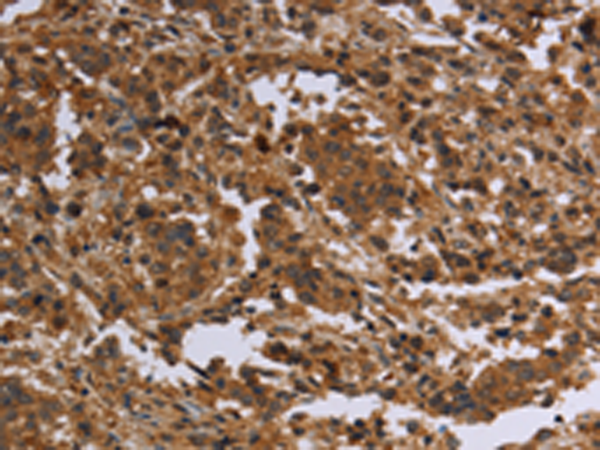

分类: 科研抗体货号: P04874别名: F1AA; F1A-ALPHA; FEM1-beta应用: WB,IHC反应种属: Human, Mouse, Rat